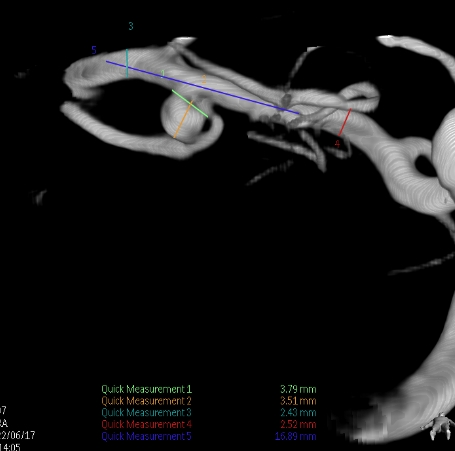

右侧颈总造影:右侧大脑中动脉瘤

右侧大脑中动脉瘤,瘤颈处发出颞支,颈宽3.79mm,瘤高3.51mm,远近端载瘤动脉直径分别为2.43mm、2.52mm。